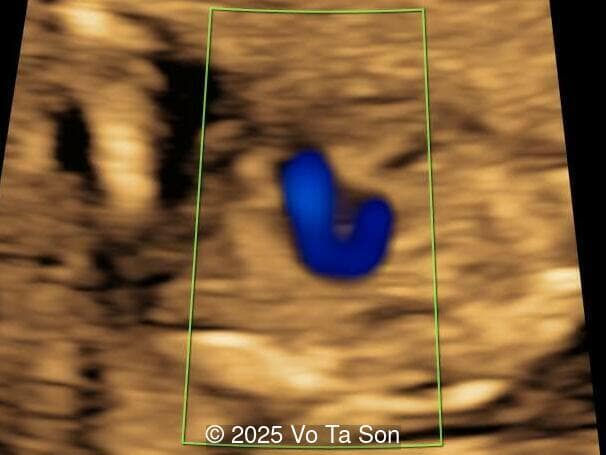

We present a case of Triploidy with a 69,XXY chromosomal complement and open spina bifida in the first trimester.

• Ventricular septal defect (VSD)

• Tricuspid valve regurgitation

• Right aortic arch

If a triploid fetus survives to the second trimester, structural anomalies can be detected by ultrasound and occur in approximately 44-49% of fetuses [4,11]. These include anomalies of the extremities (syndactyly of the third and fourth fingers, clubfeet), central nervous system (holoprosencephaly, Dandy-Walker malformation, agenesis of the corpus callosum, neural tube defects), face (micrognathia, microphthalmia), as well as omphalocele, cardiac anomalies, and renal anomalies [6,7]. The most common findings are syndacyly, occurring in approximately 70% of cases [11], and central nervous system anomalies, which are found in approximately 40% of cases [11], with myelomeningocele found in 9-13% of fetuses with triploidy [8,11-12]. Cardiac defects occur in 13%, of which 9% are ventricular septal defect [11]. If these defects are seen in a growth-restricted fetus, triploidy should be considered in the differential diagnosis and amniocentesis offered, especially if the placenta is enlarged and contains cysts. Features of a partial hydatidiform mole occurs in 24-33% of cases with triploidy [4,11]. Additionally, theca lutein cysts may develop in the maternal ovaries due to high levels of human chorionic gonadotropin [6,7].